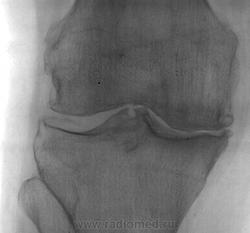

С диагнозом ДОА направлен на рентгенографию коленного сустава

Можно и ДОА написать. Повреждения медиального мениска, суставная "мышь".

По любимой вами Косинской. Щель в медиальных отделах сужена резко, остеофиты грубые. Чего не хватает?

На мой взгляд, на третью не тянет...

На мой взгляд имеется: небольшие  костные разрастания по краям латеральных и медиальных мыщелков бедренной кости и большеберцовой костях,  небольшое костное разрастание на коленной чашечке на её задней поверхности в нижних отделах. Сужение рентгеновской суставной щели, больше в медиальных отделах. Межмыщелковое возвышение заостренено. По краям замыкательных пластинок отмечается субхондральный остеосклероз.                                                                                                                               По классификации Косинской я бы поставил вторую стадию артроза коленного сустава.